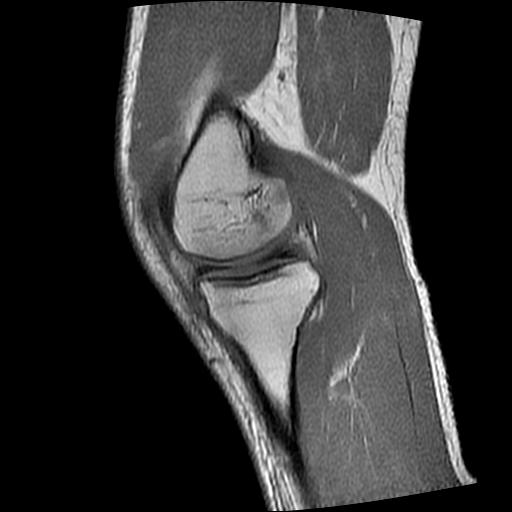

标题: MRI1265:男性40岁,右膝关节 [打印本页]

标题: MRI1265:男性40岁,右膝关节

40岁男性,右膝关节外伤,x光平片示,髁间隆突撕脱骨折。

1、前交叉韧带撕裂;

2、外侧半月板后角撕裂;

3、关节腔积液。

前交叉韧带撕裂,关节腔积液.

半月板1-2级损伤   前交叉韧带撕裂伤   关节腔少量积液  诸骨未见新鲜外伤性改变

髁间隆突撕脱骨折;内侧副韧带损伤。

内侧副韧带撕裂及关节腔积液是肯定的,但是前交叉撕裂确定吗?会不会有容积效应的因素,因为前一张前交叉显示清楚,连续性良好,且较光滑。请问楼主有关节镜支持吗?我们医院也经常有这样的患者,但苦于没有关节镜,而无法对照、证实(除非完全断裂),出现了不同的诊断结果只能毫无意义的争论。

1、前交叉韧、内侧副韧带撕裂;

3、关节腔积液。4、髁间脊撕脱骨折。

除了关节积液外并无韧带撕裂,acl胫侧附着点有2束,正常情况下脂肪信号。此病例应加做压脂像以便观察是否有骨损伤。